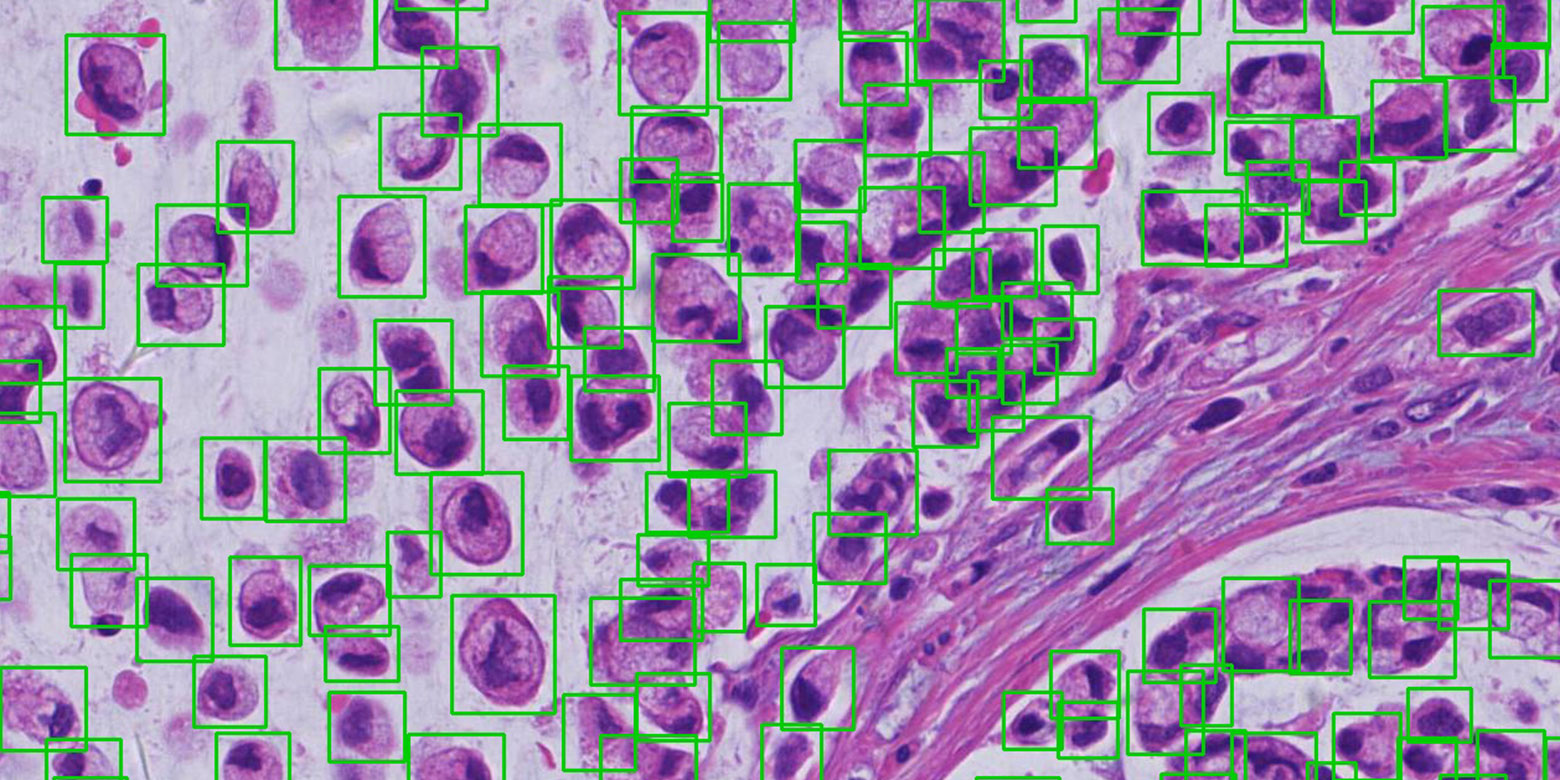

病灶/部位检测与定位

基于领先的计算机视觉技术,对 CT、MRI、病理等多种模态医学图像中的多种疾病病灶或部位进行快速检测与定位,例如基于 MRI/CT 影像的椎间盘及椎骨的定位、基于 CT 影像的肺结节检测与定位、基于病理图像的细胞检测与定位等,为医生提供诊断参考,提高诊断效率。

病灶/部位检测与定位

基于领先的计算机视觉技术,对 CT、MRI、病理等多种模态医学图像中的多种疾病病灶或部位进行快速检测与定位,例如基于 MRI/CT 影像的椎间盘及椎骨的定位、基于 CT 影像的肺结节检测与定位、基于病理图像的细胞检测与定位等,为医生提供诊断参考,提高诊断效率。